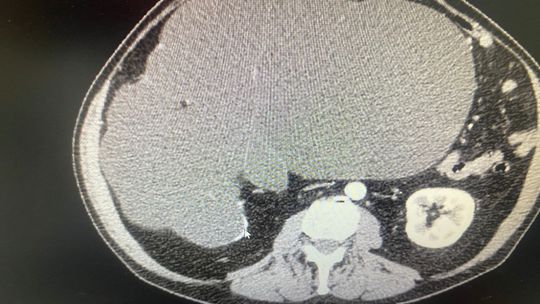

Drugi przypadek dotyczy pacjentki, która miała guza umiejscowionego w bardzo trudno operowalnym miejscu. Guz był wciśnięty pomiędzy żyłę i tętnicę nerkową, dwie najważniejsze arterie odżywcze dla nerki, przy samej jej strukturze. Istniała konieczność preparowania milimetr po milimetrze, na małej przestrzeni, z zachowaniem bardzo dużej ostrożności, z uwagi na bliskość głównych naczyń krwionośnych. Guz w całości usunięto pozostawiając nerkę w nienaruszonym stanie. Zabieg wykonano w technice klasycznej otwartej, z uwagi na wielkość guza. Pacjentka czuje się dobrze.